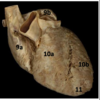

Identify the arteries

Identify #10a

Right venticle

Identify #10b

Left ventricle